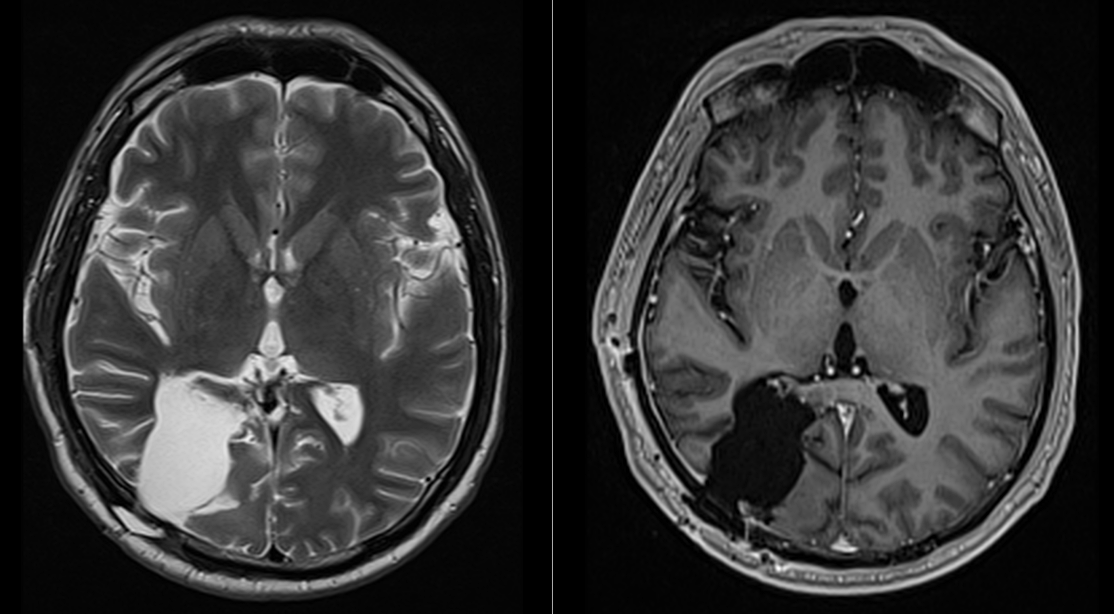

Controalele imagistice s-au repetat periodic, fiecare RMN fiind un moment de emoție și speranță.

Astăzi, la 9 ani de la operație, nu există semne de recidivă tumorală. Deficitul vizual s-a stabilizat, iar dificultățile de recunoaștere a fețelor s-au ameliorat parțial. Mai important însă, pacientul și-a recâștigat viața de zi cu zi.